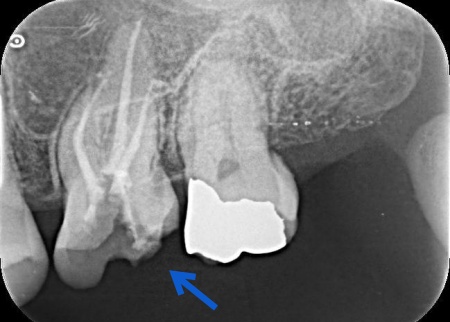

まずは、左上奥歯に装着されていた既存の詰め物を取り外し、根管内部を確認します。

続いて、マイクロスコープを使用しながら専用の器具を用いて根管内の感染した組織を丁寧に除去し、消毒薬で根管内を十分に洗浄します。

感染が広範囲に及んでいたため、複数回にわたり洗浄と消毒を実施しました。

根管内部の洗浄と消毒が完了したら、根管の内部を密封する処置を行います。

今回は、歯とのなじみがよく、歯根の先や複雑な形の部分にも適応しやすいMTAという材料を使用しました。

最後にレントゲン撮影を行い、根管がしっかりと封鎖されていることを確認して、治療を終了しています。